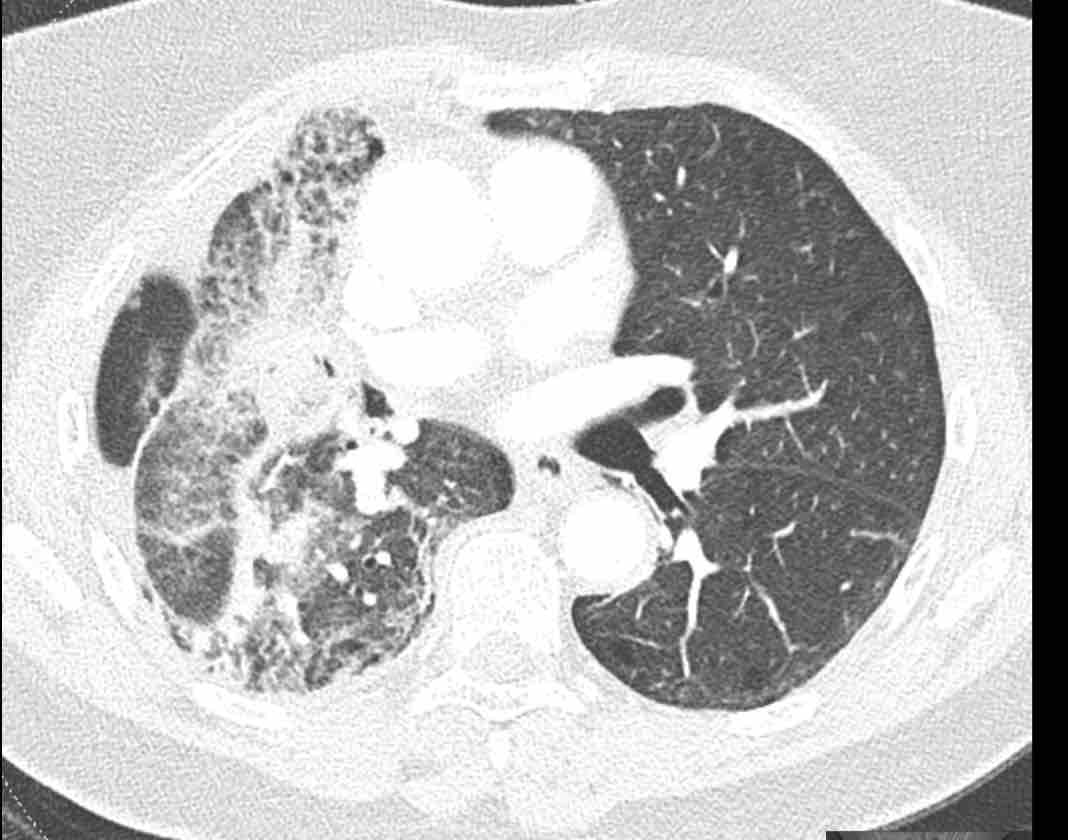

Những thay đổi cấu trúc lan rộng ở nửa ngực phải sau hóa xạ trị cho ung thư phổi không tế bào nhỏ (NSCLC) giai đoạn 4.

Theo dõi đường đi của các phế quản cho thấy thùy trên phổi phải phần lớn còn thông khí, trong khi